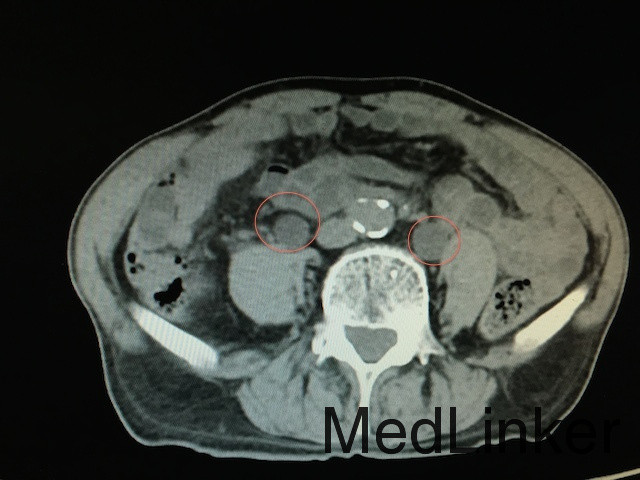

膀胱ct,尿道ct

膀胱ct图片

病理膀胱ct讨论病例2

ct13895m79典型膀胱癌一例

膀胱癌(低级别非浸润性尿路上皮癌)

辅助检查:泌尿系ct(如下图所示):膀胱实性占位,增强扫描肿物呈不均匀